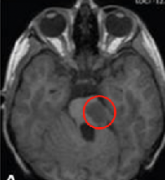

附件是2023年11月23日的MRI截图。这些图像确实显示了在苏州手术一年后的良好发现。低级别胶质瘤被完全切除,我们没有发现任何残余,附近的大脑结构和...

33岁的H女士在怀孕期间因严重头痛,走路不稳,记忆力减退等症状就医,MRI图像显示在她的两个侧脑室后部有一个较大的囊性肿瘤,立即进行囊肿排空和肿...